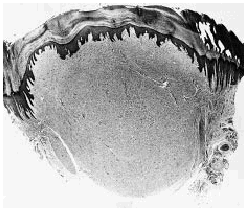

El estudio hispatológico demostró un nódulo dérmico bien delimitado, pero no encapsulado (Fig. 1), constituido por haces de colágena hialina y eosinófila dispuestos en algunas áreas con un patrón estoriforme y separados por grietas con abundante contenido de mucina y ausencia de tejido elástico. En la lesión se observaba escasa celularidad, pero existían numerosas células gigantes multinucleadas dispuestas entre los haces de colágena y especialmente abundantes en las áreas superficiales de la lesión (Fig. 2). Estas células multinucleadas mostraban un citoplasma amplio y eosinófilo y muchas de ellas tenían un contorno poligonal o estrellado con bordes angulosos. Los núcleos de estas células multinucleadas eran monoformos y no se observaban atipias ni figuras de mitosis. Desde el punto de vista inmunohistoquímico las células multinucleadas mostraban positividad para la vimentina, pero eran negativas para la proteína S-100, las citoqueratinas AE1/AE3, la actina muscular específica y el factor XIIIa.

FIG. 1.--Nódulo dérmico hipocelular bien delimitado, aunque no encapsulado.